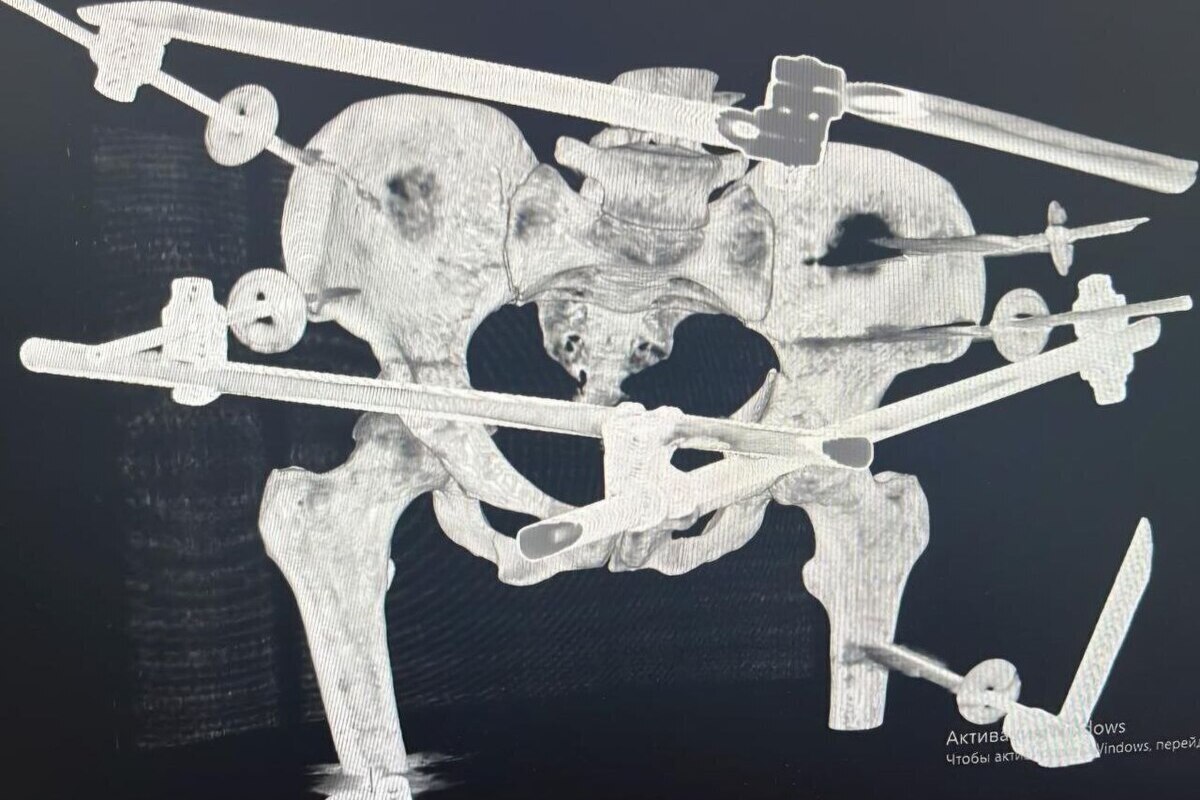

После стабилизации состояния врачи провели сложнейшую операцию: наружную и внутреннюю фиксацию переломов таза и голени, лапароскопию для исключения повреждений внутренних органов, а также первичную обработку ран. Операция прошла без осложнений.